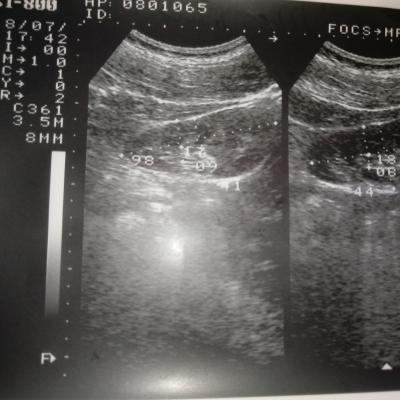

Добрый день! Моему сыну 15 лет. В его моче обнаружено большое количество эритроцитов. Узи почек показало "МКД обеих почек и киста правой почки". Назначение терапевта: уродан 1 ч/л×100 мл.×2 р.д. 30 дней,конефрон 1 таб×3 р.д. 30 дней. Скажите, пожалуйста, насколько это серъезно? Дело в том, что мой сын поступает в военную школу. Сами понимаете, там физические нагрузки. Можно ли нам там учиться с таким диагнозом? И какое лечение посоветуете? Нужно ли нам дополнительно сделать КТ или МРТ?

Ответ врача